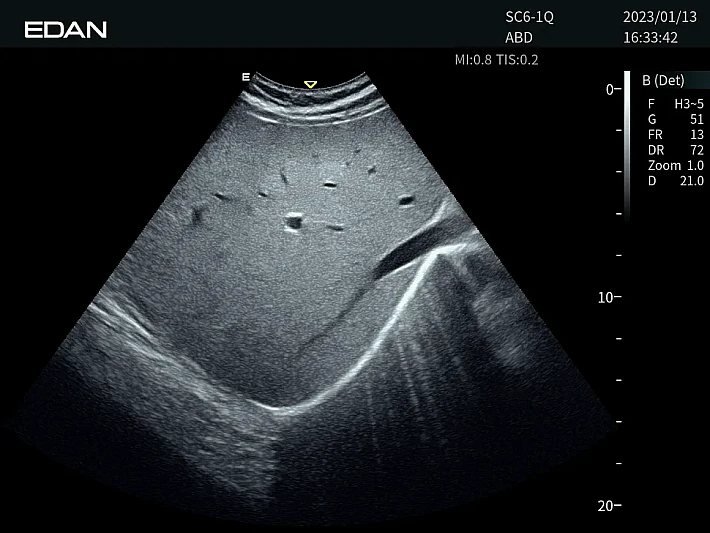

Медицинское оборудование и сервисное обслуживание